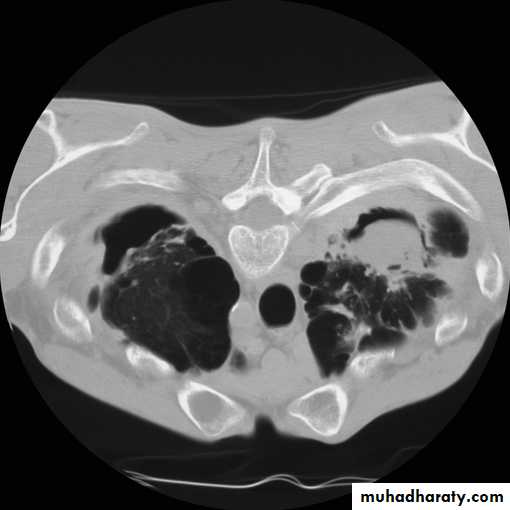

mediastinal window bone window lung window